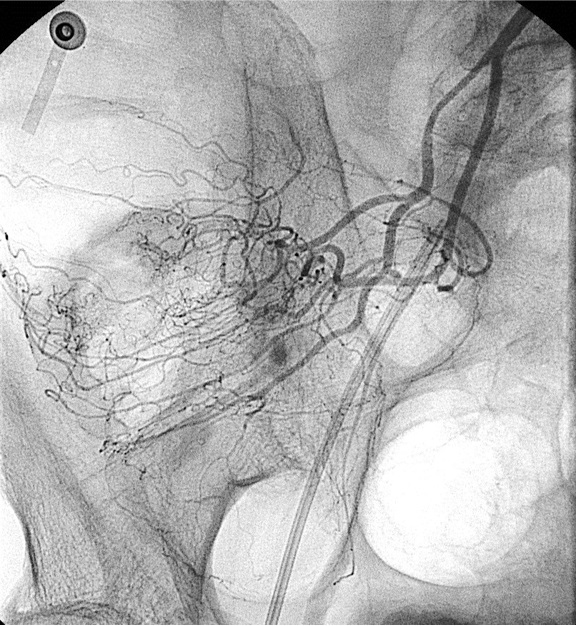

病例二:结肠憩室急性大出血(微导管接近出血)

64岁 男性 无相关病史。因下消化道出血急诊室就诊。考虑到急诊出血情况下效果差,未进行结肠镜检查。CTA 未显示造影剂外溢,但右结肠/回肠大憩室。临床持续出血和生命体征恶化,介入医生会诊决定进行动脉造影。

造影剂外溢